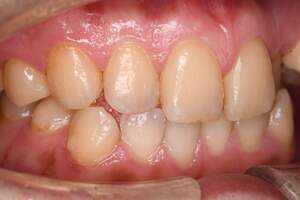

歯石除去

治療前

治療後

| 年齢 | 25歳・男性 |

| 主訴 | 歯石をとりたい・検診 |

| 治療内容 | 各種検査・歯石除去 |

| 治療期間 | 60分 |

| 費用 | 初診料3,000〜4,000円前後 +歯石除去約1,000円 |

| リスク・副作用 | ・処置後に歯がしみることがあります。 ・歯と歯の間に隙間ができるので、息が漏れ発音しにくいと感じることがあります。 ・歯ぐきの炎症が軽減すると歯ぐきが引き締まり、歯が長く見えることがあります。 |

| 担当者所見 | 前歯の裏側にすぐに歯石が溜まってしまいザラザラして気になるとご相談いただいたので適切な歯ブラシの当て方とフロスの通し方をお伝えさせて頂きました。 |